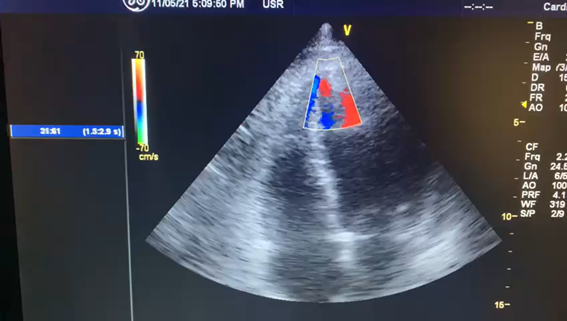

Ecocardiograma: evidencia o defeito do septo interventricular em (A) e o shunt da esquerda para a direita em (B):

B: shunt esquerda-direita